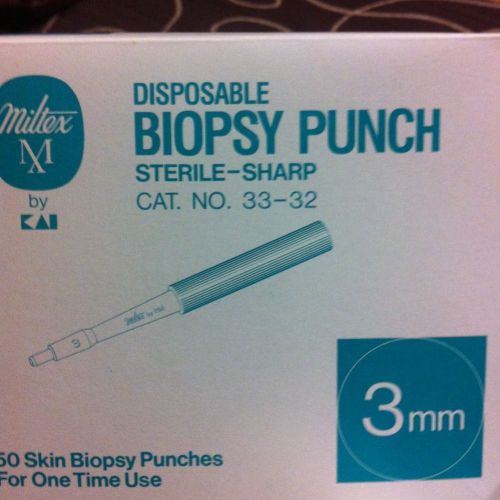

MILTEX STERILE DISPOSABLE BIOPSY PUNCHES, 3mm, 13/bx,#33-32